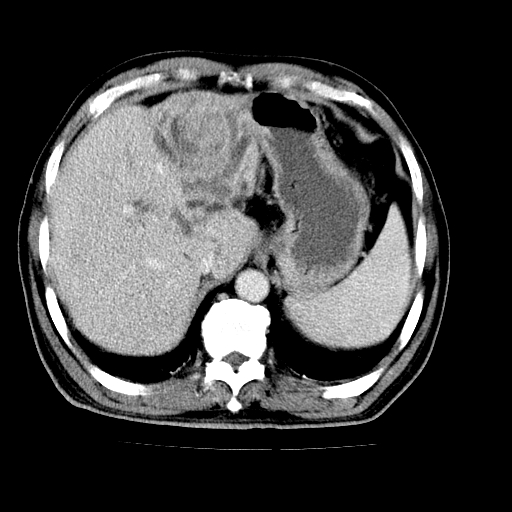

男,66岁,上腹部不适、黄染一周。彩超示:肝左叶占位,肝内胆管扩张,胆总管扩张,胆总管占位?

肝左叶不规则软组织肿块影,边缘不规整邻近肝实质受累分界不清;肝内胆管(左叶)明显扩张成“软藤状”,诊断:肝左叶胆管细胞癌。

肝左叶占位性病变,并胆管扩张,符合胆管细胞癌ct表现,门脉左支受累,左肾囊肿。窗宽太窄了,其他的看不清

左叶胆管细胞癌累及胆总管,门脉左支受侵,慢性胆囊炎胆结石,左肾小囊肿